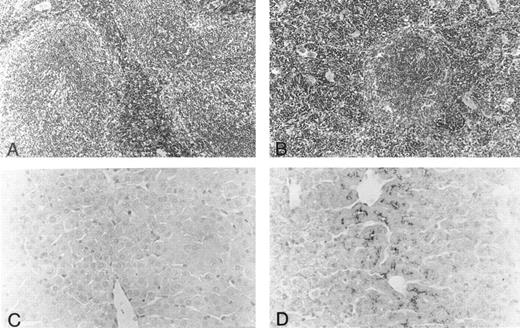

Histology.Body organs of fit1 mice appeared normally developed; however, fit1 mutant livers were detectably pale, and splenomegaly was present in most fit1 hemizygotes. Indeed, spleens from fit14397SB mutants composed an average of 1.87% ± 0.78 (n = 5) of the total body weight, whereas the mean weight of the normal littermate (cch +/cch +) spleens was 0.42% ± 0.09 (n = 5) of mean body weight (means are significantly different, P < .05). The spleens of fit14397SB mice had significant extramedullary hematopoiesis (EMH), characterized by a greater number of erythroblasts and poorly defined borders between the red pulp and white pulp, as opposed to the characteristic pattern seen in the spleens of wild-type mice (cch +/cch +) (Figs 2A and B). No EMH was seen in fit1 mutant liver (data not shown). Additionally, the fit1 mutant livers stained strongly for iron, compared with tissues from their wild-type littermates (Figs 2C and D). To a lesser degree, iron deposits were also observed in fit1 mutant spleens, and no iron deposits were seen in fit1 mutant bone marrow (data not shown).

Histology of spleen and liver from fit1 mutant mice. (A and B) Photomicrographs of hematoxylin and eosin-stained sections of (A) wild-type littermate (cch +/cch +) and (B) fit14397SB spleen. Erythroid precursors (darker staining cells) appear to be present in larger numbers in the fit1 mutant spleen, and in the mutant spleen, the white pulp areas appear smaller and less well defined. (C and D) Photomicrographs of Prussian blue stained sections from wild-type littermate liver (C) and fit14397SB mutant liver (D). Increased iron stores can be seen in the fit1 mutant liver as dark staining within several cells.

In contrast to the fit1 mutant spleens, there was no increase in hematopoietic activity in fit1 mutant bone marrow (data not shown). Additionally, thymic sections from fit14397SB mutants showed no gross structural abnormalitites, however, thymic mass varied greatly among individual mutants (data not shown). Also, no lesions or other evidence of cell destruction were detected in fit1 mutant skin or other organs.